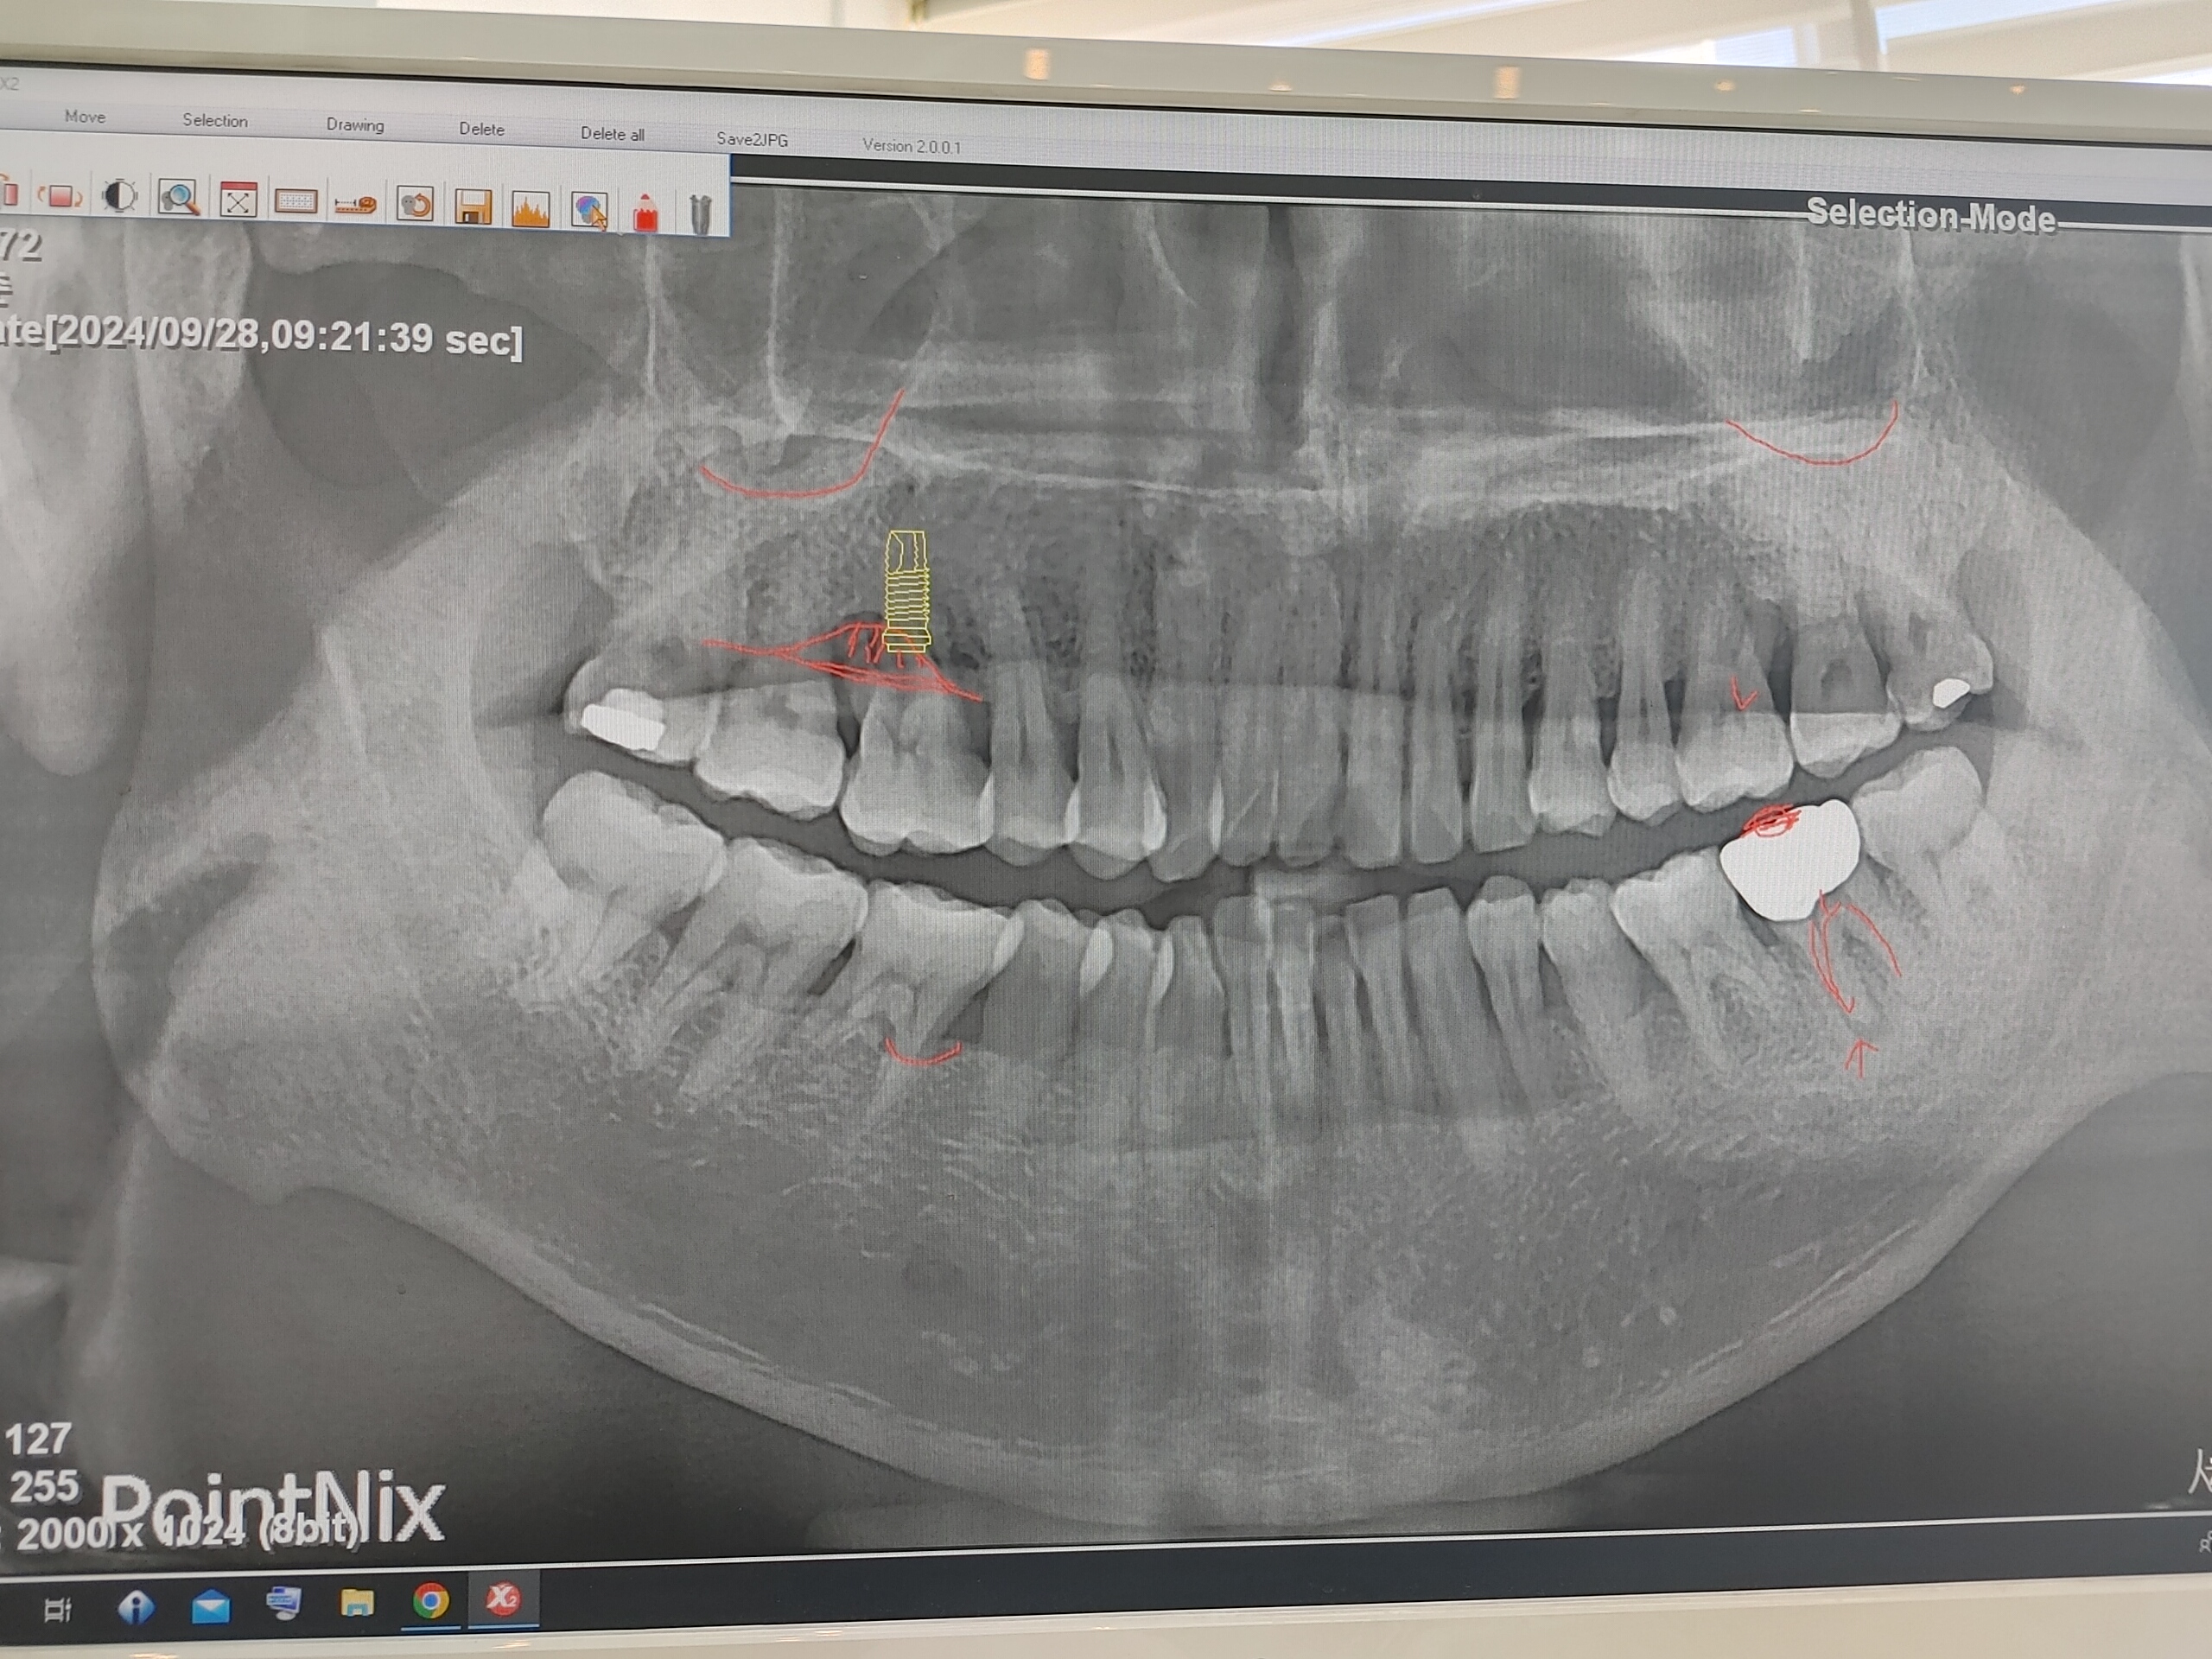

심었어요 ^^

인플란트 뿌리를 윗잇몸에 팍 팍 심었어요

이 사진은 뿌리 밖고서 사진 찍었던건 같은데 @.@ .......

그 사진을 내가 찍었던거 같은게 정말 모르겠어요 ^^